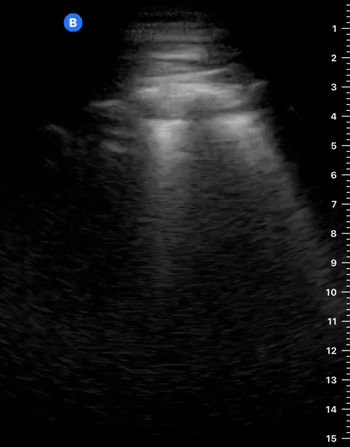

IS THERE LUNG SLIDING?

This profile is characterised by absent lung sliding and present A-lines. The finding of dynamic lung sliding rules out the presence of pneumothorax. In addition, the finding of the B lines artefact indicates indemnity of both pleural layers and rules out the presence of pneumothorax.

When there is a pneumothorax, the pleural layers are separated by air. Ultrasound waves are reflected at the encounter of the parietal pleura, which lies upon the air of the pneumothorax itself. Therefore, movement of the visceral pleura and lung deep to the pneumothorax cannot be seen, leading to loss of the typical shimmering, dynamic appearance.

ABSENT LUNG SLIDING

Although it is usually a key feature of pneumothorax, the absence of dynamic lung sliding lacks specificity and can also be found in other conditions such as apnea, atelectasis, bullae, chronic airflow limitation, pleurodesis, inflammatory adherences, fibrosis, right main-stem intubation, oesophagal intubation and cardiopulmonary arrest.

LUNG POINT

Conversely, the lung point sign is pathognomonic and 100% specific for pneumothorax. It represents the transition point where a normal lung gives way to pneumothorax: sliding is present on one side of the image while absent on the other. Additionally, the lung point indicates pneumothorax volume: moderate if anterior, massive if posterior or absent. Lateral lung points correlate with a 90% need for drainage versus 8% with anterior lung-point (11).

The M mode is far from essential but can be helpful in the interpretation if you struggle to identify sliding in B-Mode. A ‘seashore image’ will be seen in the normal lung, whereas a ‘barcode image’ will appear in absence of lung sliding. Remember, absent lung sliding by itself is not diagnostic of pneumothorax.